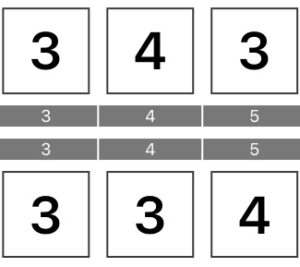

歯周ポケット検査についてですが、

健康な歯ぐきでは歯との間の溝(歯周ポケット)が2~3mm程度ですが、

歯周病になるとこの溝が深くなっていき、数値が上昇します。

つまり、歯周ポケットの数値が高い=歯周病が進行している

ということになります。

この数値が最初のレントゲン写真時の歯周ポケットの数値です。

2~3mmが健常ですから、この数値は良くないことがわかります。